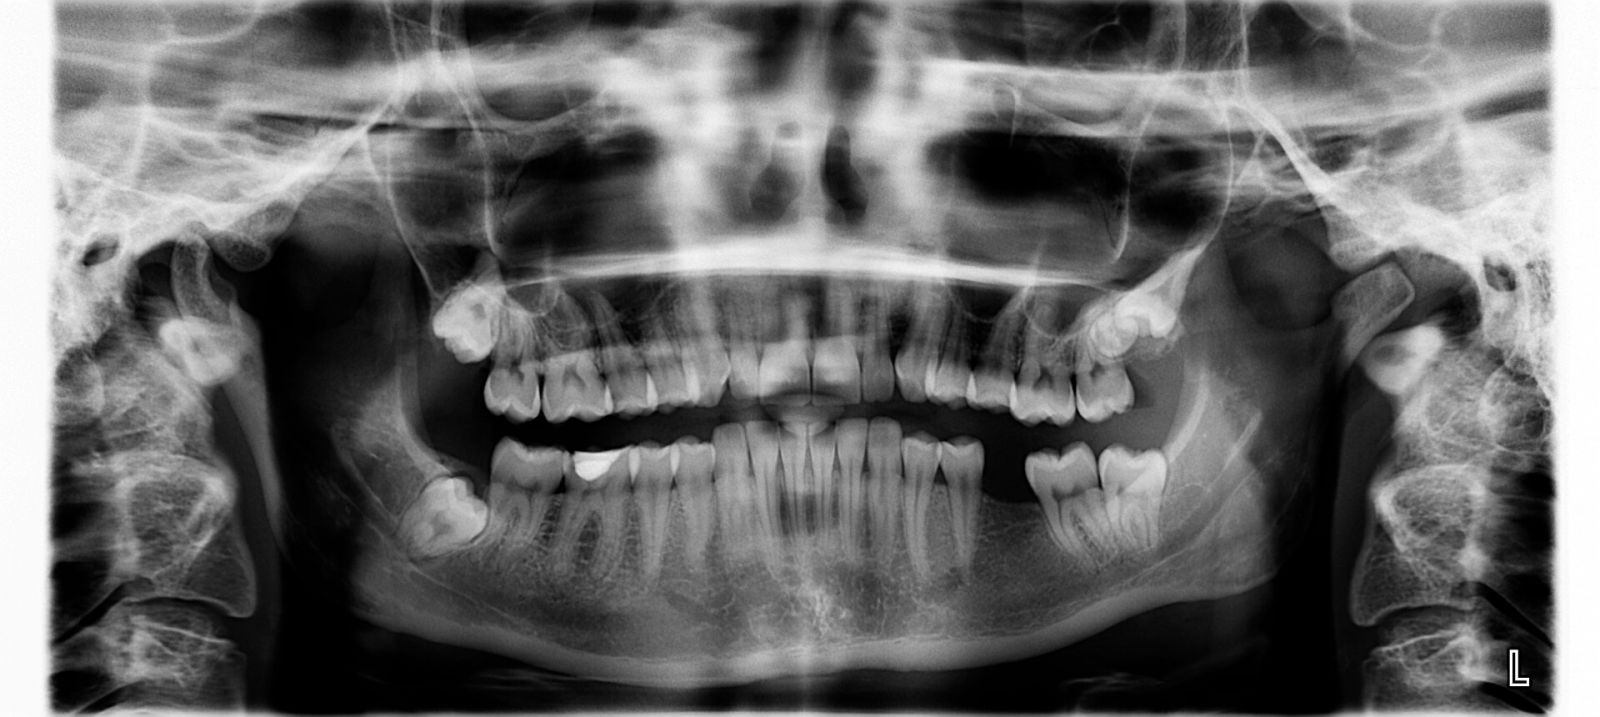

Circa il 90% delle persone ha rimosso almeno uno dei terzi molari, comunemente chiamati denti del giudizio, ad un certo punto della loro vita Molte persone hanno deciso di estrarli tutti e quattro per prevenire problemi dentali futuriSe si esegue questa procedura relativamente comune, sapere cosa mangiare dopo l’intervento chirurgico può portare a un recupero molto più agevole. La pericoronite è un’infiammazione della gengiva che circonda un dente in fase di eruzione Si tratta di un processo acuto, che quindi esordisce all’improvviso, e frequentemente si presenta a livello dei denti del giudizio, così chiamati perché spuntano tra i 18 e i 25 anni di età Pericoronite e denti del giudizio. Estrarre il molare del giudizio la preparazione L’estrazione del molare del giudizio è un atto chirurgico e in quanto tale richiede una preparazione preliminare La visita specialistica del cavo orale, supportata da un accurato studio radiografico, permette al medico di valutare con precisione la posizione e la salute del dente del giudizio.